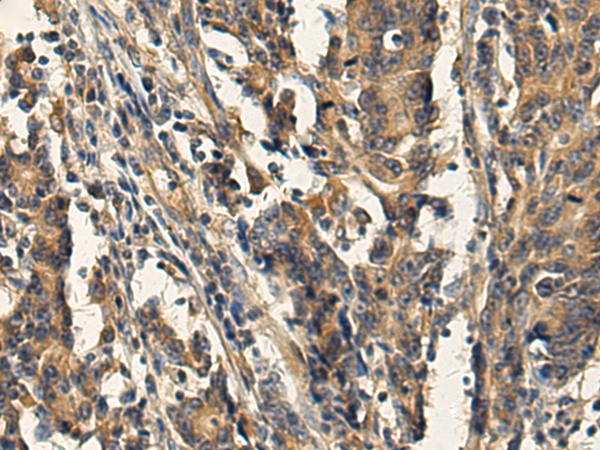

IHC (Immunohistochemistry)

(The image is immunohistochemistry of paraffin-embedded Human gastric cancer tissue using (AP3B1 Antibody) at dilution 1/130.)